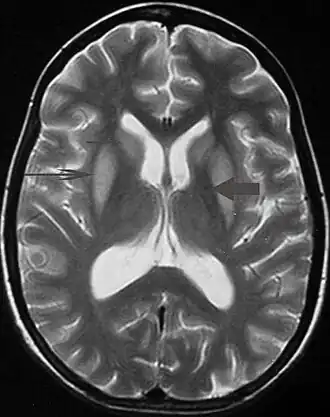

| Ressonância de um paciente com parkinsonismo severo. | |

Tremor pode ser um sintoma associado a distúrbios nas partes do cérebro que controlam os músculos de todo o corpo ou em áreas específicas, tais como as mãos. Dentre os problemas neurológicos que podem produzir tremor incluem-se: hipertireoidismo, esclerose múltipla, acidente vascular cerebral, traumatismo craniano, doença renal crônica, doenças neurodegenerativas que danificam ou destroem partes do tronco cerebral ou o do cerebelo, sendo a doença de Parkinson o mais frequentemente associados com tremor. Transtornos neurológicos que causem tremor são chamados de parkinsonismo.